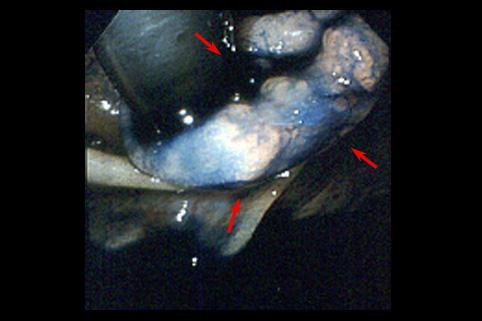

疾病(病理主体)的分类恶性上皮性肿瘤/腺癌

部位(按器官分)大肠/回盲部

检查方法内窥镜

肿瘤的肉眼分类0型(表在型)/IIa型(IIa+IIc)

肿瘤最大直径10~14

肿瘤的深度m